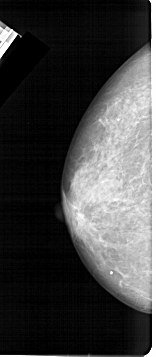

A_1473_1.LEFT_CC

LEFT_CC LINES 5341 PIXELS_PER_LINE 2326 BITS_PER_PIXEL 12 RESOLUTION 43.5 NON_OVERLAY